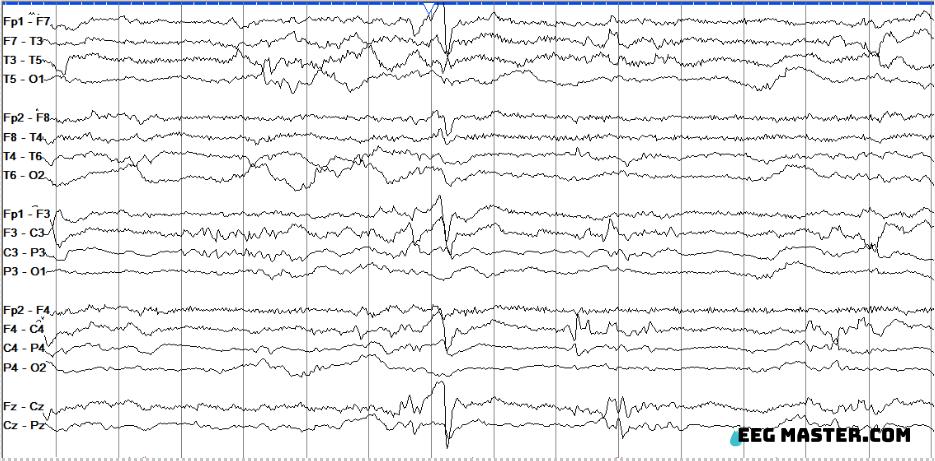

This is a 2-day-old newborn infant born at 38 weeks gestational age undergoing therapeutic hypothermia for suspected neonatal hypoxic-ischemic encephalopathy. What is the nature and name of the finding at the 8th second of this tracing (white arrowhead)?

Credit: David Lang